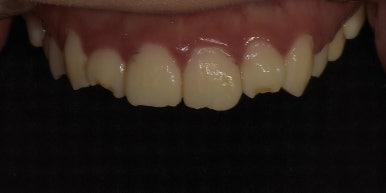

12전치 라미네이트 치료 전 최초 내원 시 모습

2023-06-23

환자분께서는 우선 웃거나 말할 때 보이는 치아 대부분을 라미네이트로 치료하고 싶어하셨습니다.

특히 오른쪽 아랫니(#42)는 치아가 기울면서 앞으로 튀어나와있어

이 치아를 다른 치아와 밸런스를 맞춰 배열을 고르게 만들고 싶어하셨는데요.

라미네이트, 올세라믹크라운 치료 전 하악 모습